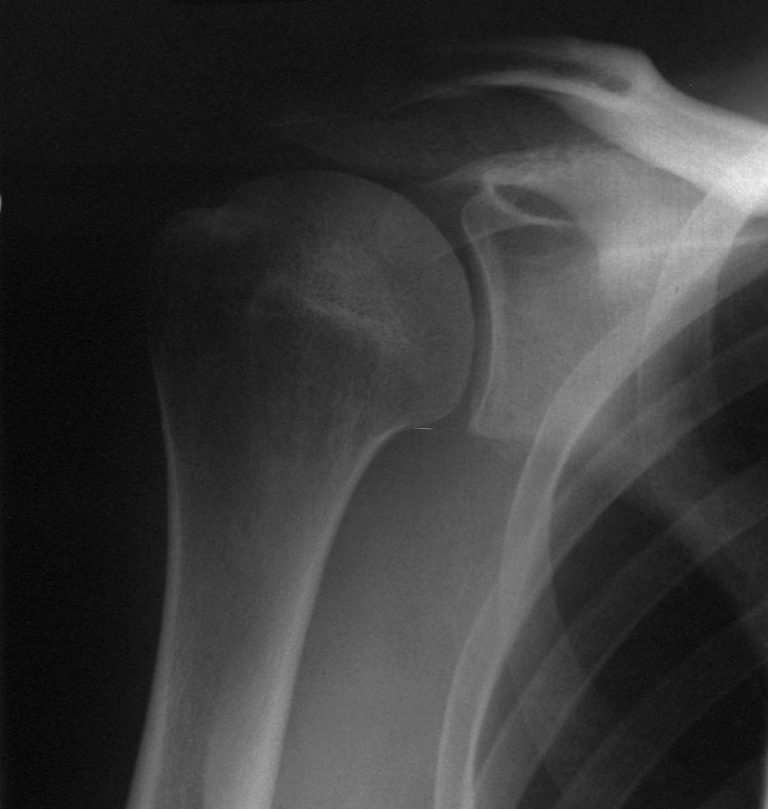

Anterior shoulder dislocation Image History Of Shoulder Dislocation Shoulder dislocations can be complete or partial, and usually occur after a trauma, such as a fall or motor vehicle collision. Traumatic anterior shoulder instability, also referred to as tubs (traumatic unilateral dislocations with a bankart lesion requiring surgery), are traumatic shoulder injuries that generally. In a complete dislocation, the joint surfaces are completely. The typical history of a shoulder. History Of Shoulder Dislocation.

Anterior shoulder dislocation Radiology at St. Vincent's University History Of Shoulder Dislocation The shoulder dislocation (more accurately termed a glenohumeral joint dislocation) involves separation of the humerus from the glenoid of the scapula at the. Shoulder dislocations are the most common of all major joint dislocations and frequently present to clinics and emergency. In a complete dislocation, the joint surfaces are completely. The typical history of a shoulder dislocation entails a sudden. History Of Shoulder Dislocation.